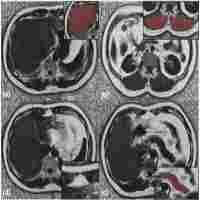

| Description | Journal: Obesity research The emerging concept that various fat compartments are metabolically active and play separate and decisive roles in the pathogenesis of coronary atherosclerosis, hypertension, insulin resistance, diabetes and stroke, has given obesity research a new direction. Of particular interest is the relative amount of intra‐abdominal fat thought to be responsible for the metabolic complications. We studied the precise fat distribution and its correlations with the metabolic parameters in 44 non‐human primates (Macaca fascicularis). Intra‐abdominal, subcutaneous, and total abdominal fat (IAF, SAF, TAF) were assessed by magnetic resonance imaging (MRI) and somatometry. Quantitative computer analyses of abdominal MRI scans revealed predominant IAF distribution. Box plot analysis of IAF and SAF revealed wide diversity in the amounts of fat, especially in monkeys with body mass index (BMI) <30 $kg/m^{2}$. Primates with similar BMI in each quartile revealed an extensive heterogeneity in IAF as well as SAF. Numerous significant correlations within site‐specific somatometric measurements as well as within the MRI determinants of abdominal fat were seen. However, only body weight correlated with IAF and skinfolds could predict SAF. After adjusting for body weight, partial correlation analysis showed a significant correlation (P<0.05) between total cholesterol and IAF. Conclusion: MRI revealed considerable heterogeneity of IAF, SAF and TAF in a cohort of primates believed to be homogeneous by somatometric definition. Male cynomolgus monkeys appear to be a valuable model for a systematic evaluation of fat. Individuals with identical body weight and height may show a diverse pattern of fat distribution. |